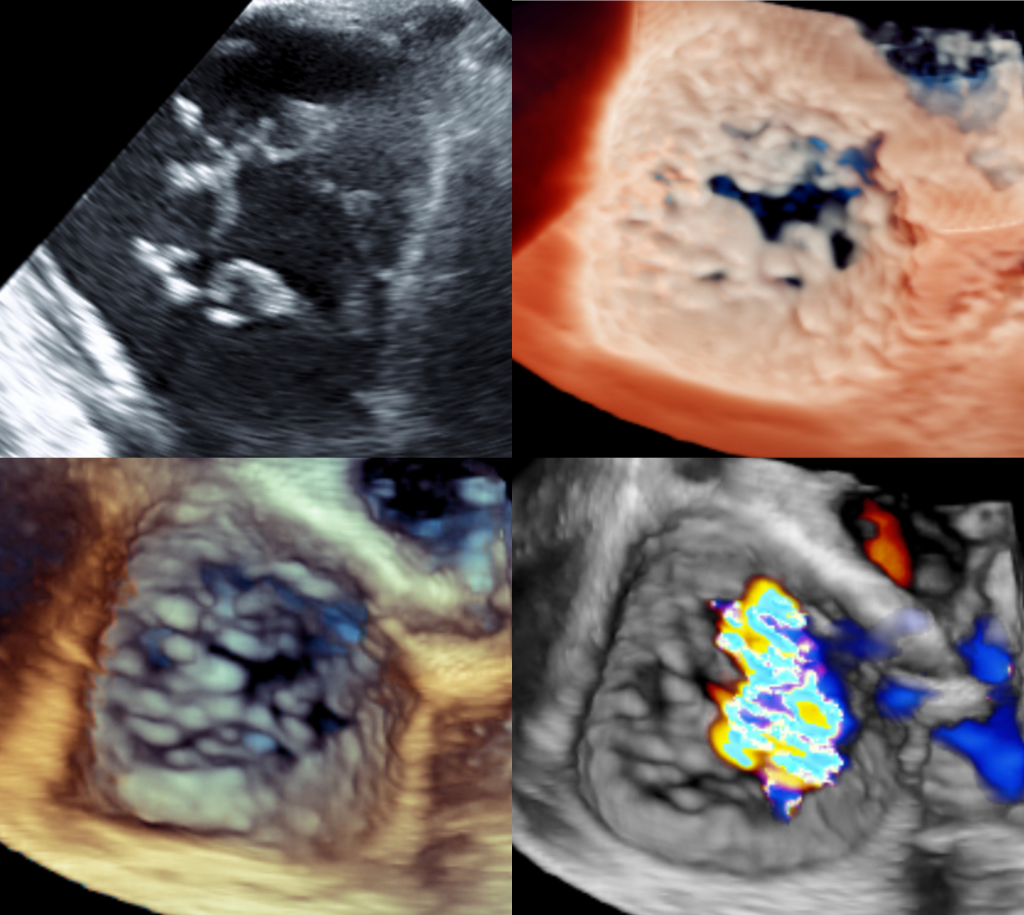

RV dysfunction (RVFAC_dichotom = 0)

Torrential TR (grade 5)

Unfavourable leaflet configuration